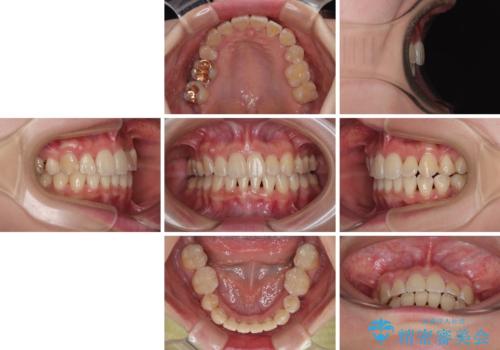

【モニター】前歯のデコボコをワイヤーの抜歯矯正で綺麗に整える

- 前歯1本が後ろ側に隠れてしまうほどのデコボコを気にして来院された患者様です。

前歯のデコボコが顕著なのはもちろんですが、左右ともに奥歯の咬み合わせに問題があり、上顎臼歯が前方位にある状態でした。

上顎は左右の第一小臼歯2本を、下顎は左右第二小臼歯2本を抜歯することで、奥歯の咬み合わせを改善しながら、デコボコを解消していくこととしました。

奥歯の咬み合わせ改善にはどうしても長期間を要します。

3年強とお伝えしておりましたが、予想通り3年3ヶ月で治療を終えることができました。